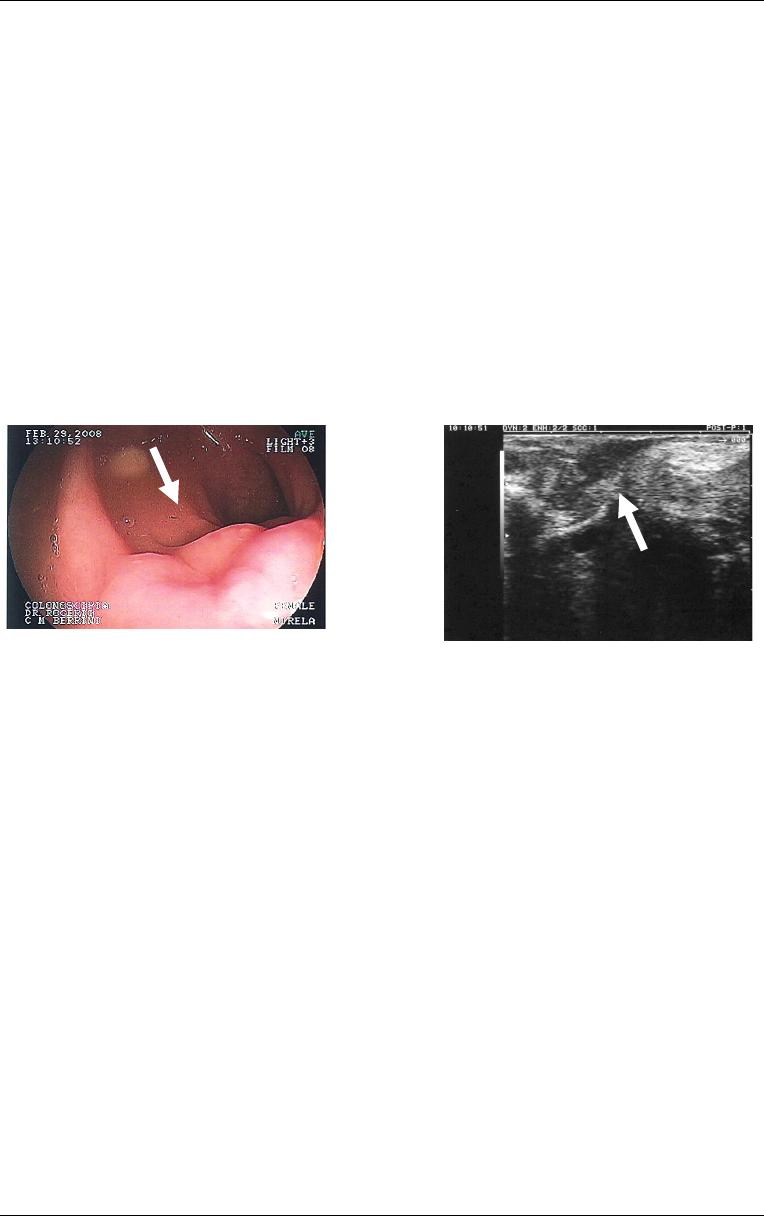

Figura

5

- Imagem

de colonoscopia

evidenciando colite

(seta) em paciente

com endometriose

intestinal. Obs.

Imagem cedida pelo

Dr. Lucio Rossini

Introdução

24

A colonoscopia é útil no diagnóstico diferencial entre endometriose e outras

doenças intestinais (Martin, Batt, 2001) (Figura 5). Os achados endoscópicos na

Figura 6

- Imagem de

colonoscopia com deformidade

em sigmóide (seta) decorrente de

endometriose intestinal. Observa-

se mucosa levemente congesta.

Obs. Imagem cedida pelo Dr.

Lucio Rossini.

7

em reto (seta) decorrente de

se mucosa intestinal normal.